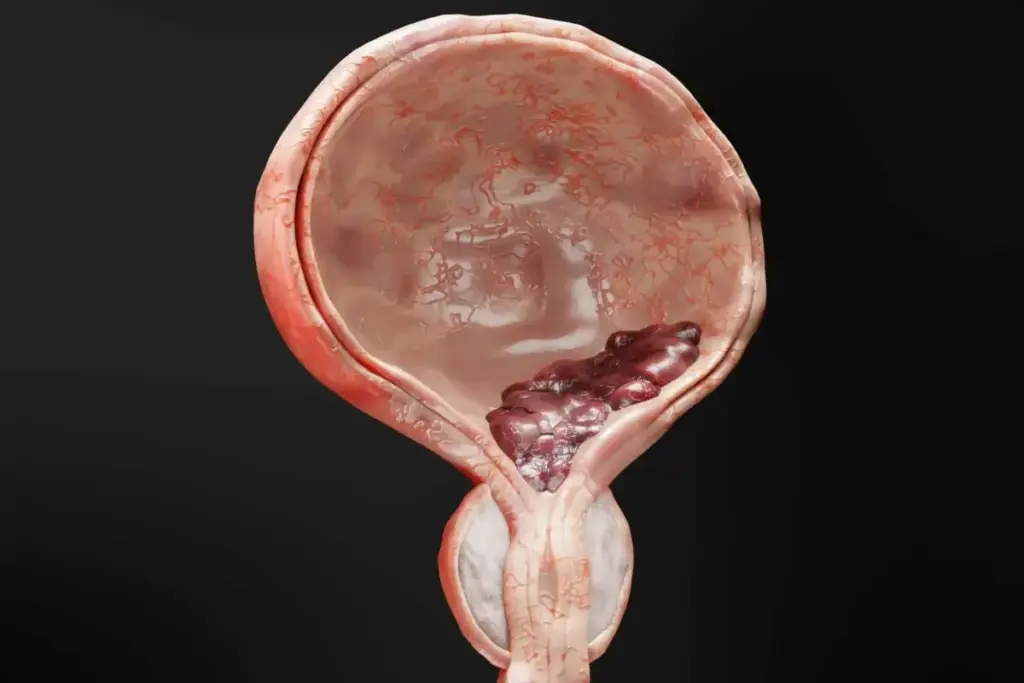

Bladder cancer is a complex condition that involves the uncontrolled growth of abnormal cells in the bladder. This type of cancer can significantly impact an individual’s quality of life, making it essential to understand its basics.

What is Bladder Cancer?

Bladder cancer occurs when the cells in the bladder lining become malignant. The bladder is a hollow organ that stores urine, and cancer can develop in its inner lining. There are several types of bladder cancer, with transitional cell carcinoma being the most common. Understanding the nature of bladder cancer is vital for effective diagnosis and treatment.